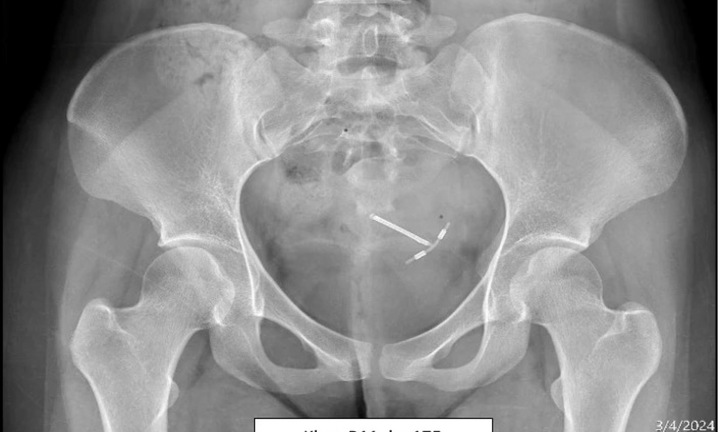

Hai vợ chồng chị N. lên Hà Nội khám, được các bác sĩ thực hiện các xét nghiệm, siêu âm, chụp tử cung vòi trứng có nghi ngờ hình ảnh những khối nhú bên trong buồng tử cung.

Để khẳng định thêm những tổn thương này, bác sĩ chỉ định chị N thực hiện nội soi thăm dò buồng tử cung và phát hiện ra tình trạng polyp nhỏ dạng chùm cần thực hiện phẫu thuật cắt bỏ. Sau khi nội soi thăm dò và làm thủ thuật cắt bỏ polyp, tái khám thấy tình buồng tử cung ổn định. Vợ chồng chị N quyết định thực hiện thụ tinh trong ống nghiệm (IVF) một lần nữa, cuối cùng may mắn đã đến để giờ đây chị N đã sinh những em bé khỏe mạnh.

Nội soi thăm dò buồng tử cung là thủ thuật đưa một ống soi vào buồng tử cung để chẩn đoán kết hợp với điều trị tổn thương. Thủ thuật này được chỉ định nhiều trong chẩn đoán các bất thường bên trong buồng tử cung ở những trường hợp vô sinh nữ. Nội soi buồng tử cung giúp đánh giá hình dạng, kích thước buồng tử cung chính xác nhằm xác định nguyên nhân gây vô sinh.

Kỹ thuật nội soi thăm dò buồng tử cung giúp chúng ta có thể phát hiện được 99% các tổn thương trong buồng tử cung bằng cách nội soi trực tiếp từ ống cổ tới đáy buồng tử cung và hai lỗ vòi tử cung để xem có tổn thương, kích thước, màu sắc, mật độ như thế nào, từ đó phát hiện bệnh lý và điều trị kịp thời.